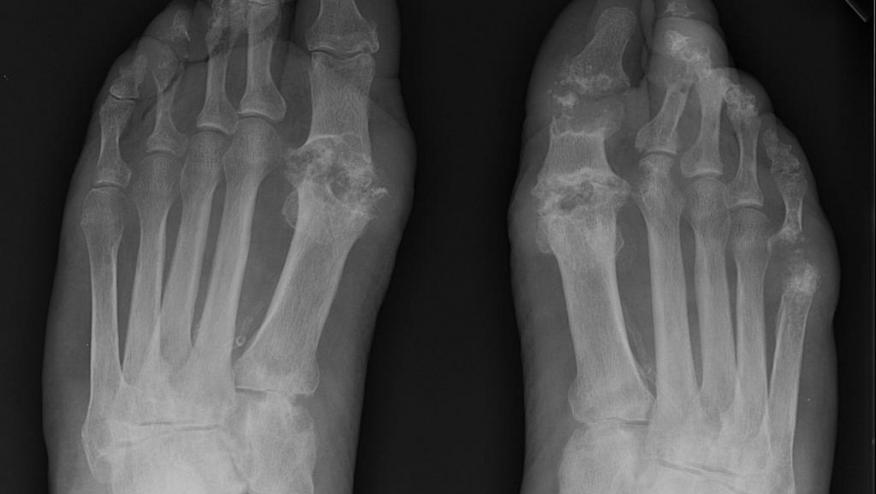

A randomized controlled trial in gout patients has shown that starting febuxostat during an acute gout flare was without ill-effects and did not prolong the gouty attack.

A multicenter, randomized, placebo-controlled, trial enrolled 140 gout patients with an acute gout flares within 72 hrs and randomized (1:1) them to either placebo or febuxostat (40 mg/day). Acute gout was also managed with diclofenac (150 mg/day) for 7 days and then open-labelled on the eighth day.